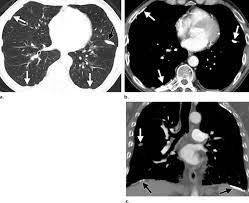

Examples Of Pleural Plaques On A A Chest Ct Arrows Indicate Pleural Download Scientific Diagram

Examples Of Pleural Plaques On A A Chest Ct Arrows Indicate Pleural Download Scientific Diagram from www.researchgate.net